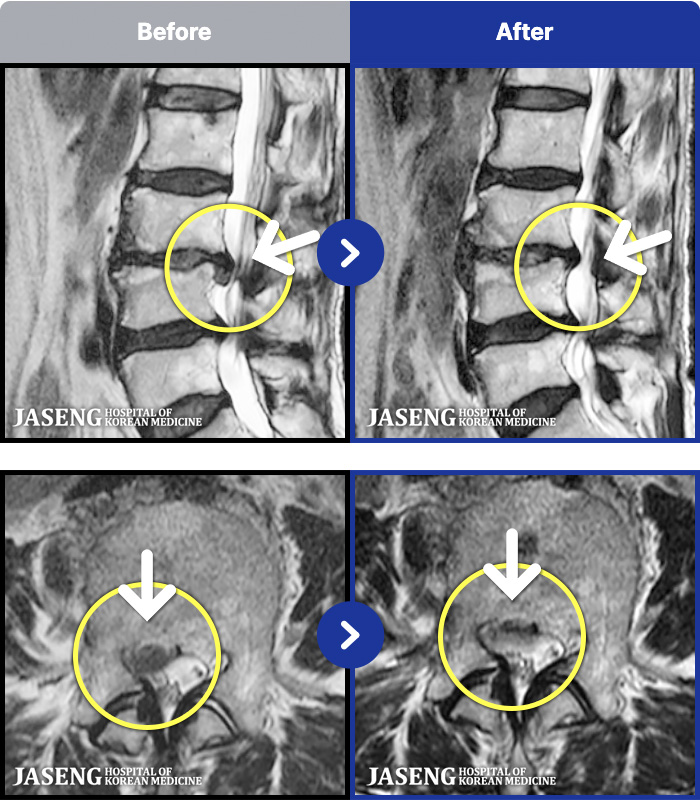

MRI ġ

1,304 MRI ũ ʸ Ȯϼ.